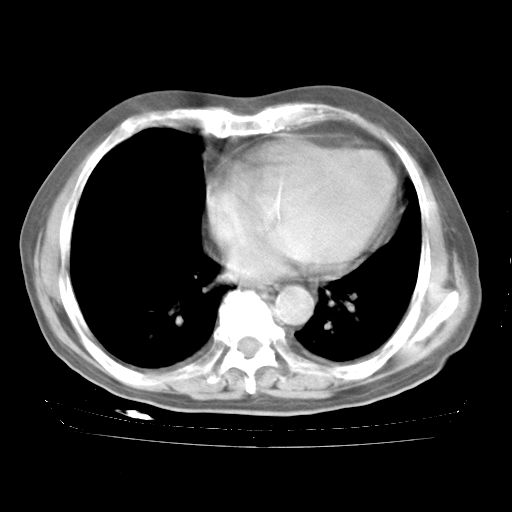

今天部分检查

轻微咳嗽,无痰,(体温正常时)R20次/分,P75次/分,双肺底、腋下可闻及少量捻发音。下肢轻度浮肿。

血常规:白细胞9.11×109/L,N0.92,L5.64,血小板39.2×109/L,HB148g/L,ESR2mm/H。

尿常规:潜血+

血生化:总蛋白69.71g/L,白蛋白38.40g/L,球蛋白31.31g/L,CRP27.9mg/L,尿素氮11.98mmol/L,肌酐106μmol/L,乳酸脱氢酶1099 U/L,肌酸激酶108U/L,CK-MB 61U/L。

腹部B超:胆囊壁增厚,肝、胆、胰、脾、肾无异常,肠系膜淋巴结、腹膜后淋巴结无增大。

ECG:右心室增大

心脏超声检查:无右心室增大。

增加治疗:异烟肼、利福平、乙胺丁醇,静滴左氧氟沙星、参麦注射液。甲强龙从80mg暂减为40mg。

强的松3月1日改为10mg qd,4月1日改为10mg qod。3月份以前的减量过程和环磷酰胺疗程需等明天查看记录(我岳父自己做的记录在他家里)。